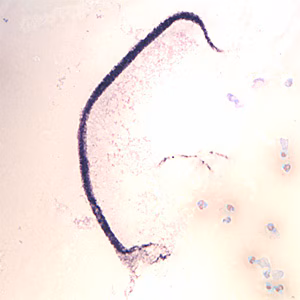

A 21-year-old female presented with swelling of the eyelid, wrist, and knee. The symptoms started after returning from a three-month trip to Cameroon in 2011. A blood specimen was collected by her health care provider at 11:30 A.M. and smears were made and stained (NOS). Her eosinophilia at the time was 48%. A filarial IgG4 antibody test performed a month prior and was negative. Two worm-like structures were observed by laboratory technicians after scanning 10 stained thick smears. Images of both structures were captured (Figures A and B) and shared with CDC personnel. As follow-up to the images, a tube of EDTA blood was sent to the DPDx Team for further evaluation. Figure C shows what was found on a wet mount of the blood; Figures D and E are from thick and thin Giemsa-stained smears, respectively. What is your diagnosis? Based on what criteria?

Figure A